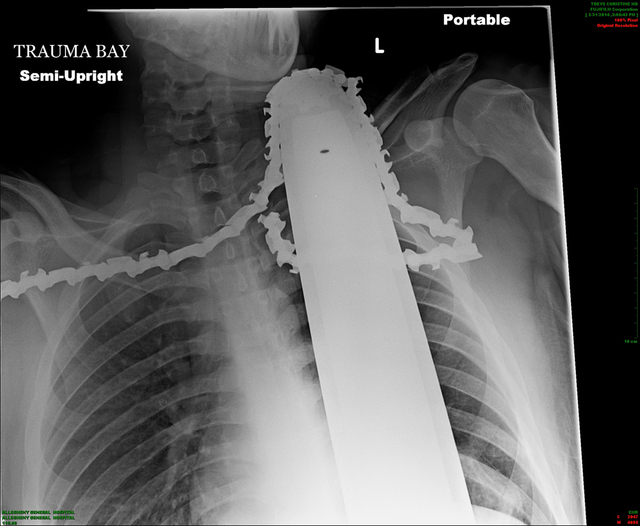

Valentine had emergency surgery at Allegheny General Hospital. Doctors say the saw missed major arteries and instead cut into muscle. The hospital Tuesday released an X-ray showing the saw still in the 21-year-old’s neck.